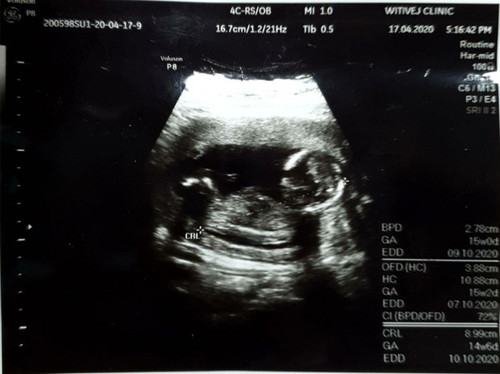

อัลตราซาวนด์ครั้งแรก หมอบอกยังไม่แน่ใจเรื่องเพศค่ะ

รบกวนแม่ๆที่มีประสบการณ์ดูให้หน่อยค่ะ ว่าเพศญ/ช ได้ 14w แล้วค่ะ

ไม่ชัดเลยค่ะ อดทนรออีกนิดนะคะ รอบกน้าเห็นชัดแล้วค่ะถ้าน้องไม่หนีบ

ต้องเป็นรูปหว่างขาน้องค่ะ

รอไปฝากครรภ์คงได้ทราบ ขอบคุณค่ะ